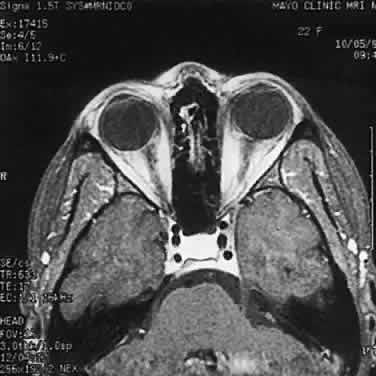

Modern imaging techniques have greatly facilitated the evaluation of optic nerve sheath meningioma and glioma.29 Plain orbital radiographs occasionally show abnormalities of the optic foramen and calcification. Imaging studies (CT and MRI) show diffuse tubular or less commonly, globular enlargement of the nerve sheath complex (Fig. 43).49,50 As with its intracranial counterpart, the optic nerve meningioma typically enhances brightly. “Tram-tracking” results when the thickened sheath outlines the uninvolved central nerve from which it is sharply demarcated. Although characteristic of optic nerve meningioma, this is not specific and can be seen in inflammatory conditions and rarely even in optic nerve glioma. Precise localization of the extent of the tumor is determined with MRI studies, particularly with fat-saturation techniques. Dilation of the anterior perioptic space (perioptic cyst) between the anterior edge of the tumor and the globe is seen in instances in which the tumor does not encroach on the globe and is a distinct and common feature.51,52

Fig. 43. Primary meningioma of right optic nerve. Computed tomography.